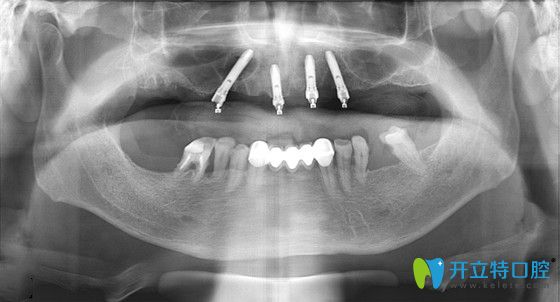

張大爺在東營鉑爾口腔做種植牙后的CT片

張大爺即刻負(fù)重手術(shù)過程全記錄:首先,吳院長運用了三維數(shù)字軟件,精準(zhǔn)的測量了張大爺?shù)难啦酃敲芏?、高度、寬度等信息,確定了種植位置,經(jīng)過1個多小時,復(fù)雜而有序的專業(yè)操作后,完成了種植體的種植操作;然后又為張大爺安裝了基臺、牙冠;當(dāng)天回到家就能吃東西啦!